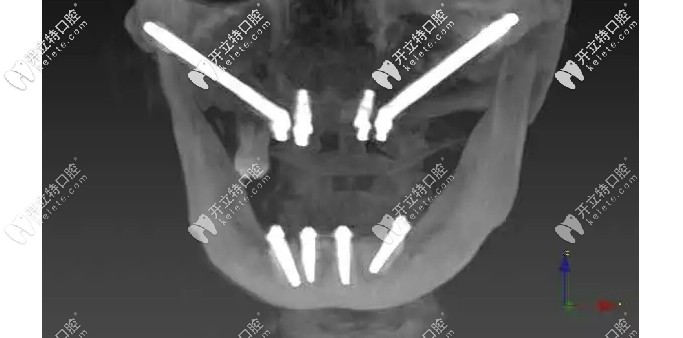

面對(duì)這種情況,想要做種植牙就要進(jìn)行穿顴種植,首先要了解顧客的身體情況;為了確保手術(shù)的能成功,需要制作3D打印頜骨模型,然后數(shù)碼設(shè)計(jì)術(shù)前導(dǎo)板......

術(shù)中,植體一段穿過(guò)顴骨另一端平放置在盡可能接近牙槽嵴頂?shù)奈恢?,且種植體有一個(gè)45°的轉(zhuǎn)角基臺(tái),就算在頜骨極度缺失的情況下,不植骨也可以馬上種植即刻修復(fù)哦!